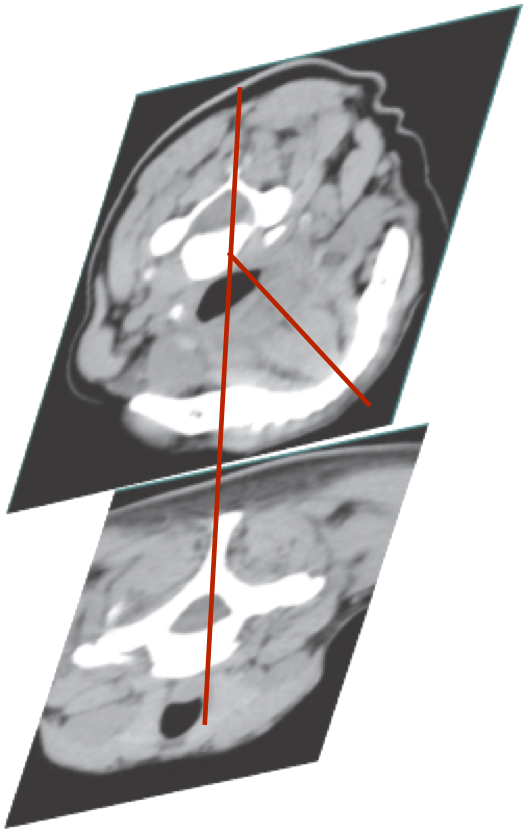

CAPUT-COLLIS CONCEPT

TORTICAPUT

C3

C7

Head rotated via C1-2 {Atlanto-axial joint}

C3-7 vertebral column column no movement

TORTICOLLIS

C3-6 rotate with C1-2 and head

The larynx is not above the sternum

AXIAL ROTATION-TORTI

ROTATION OF HEAD